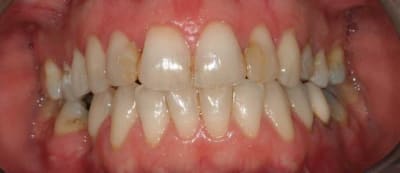

je vais démonter cette contention et essayer de faire un peu mieux que ça.

quelle est la meilleure méthode pour faire une contention au maxillaire, sachant que les latérales vont sûrement avoir des facettes ou des couronnes.

-fil de fer?

-ribbond?

-autre?